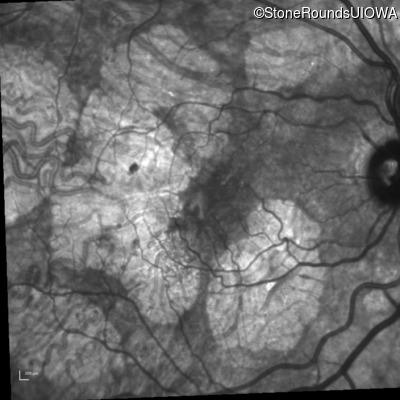

Infrared Fundus Photograph - Left - 20/40 +1

Exemplar